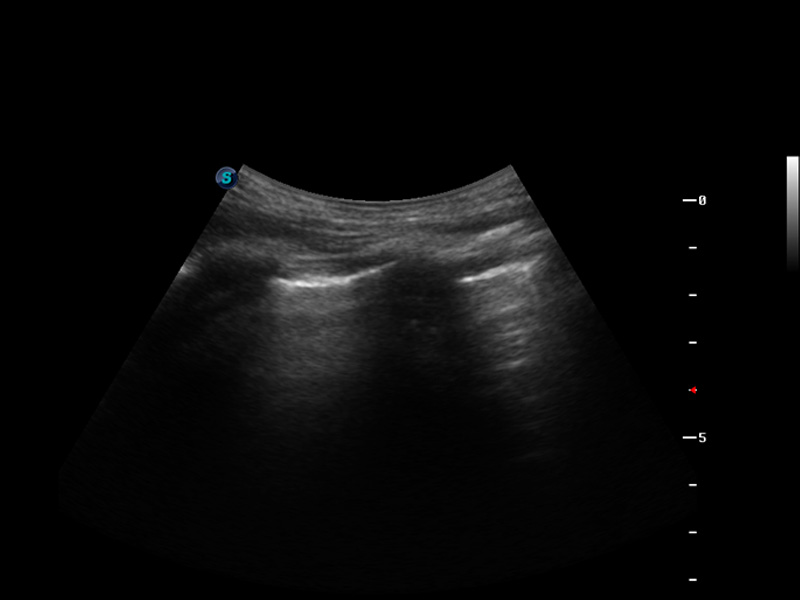

S9便携式彩色多普勒超声诊断仪是米兰官方网站研发的高端便携彩超设备,外观设计新颖、产品性能卓越。S9在便携超声领域采用了突破传统的触摸屏交互设计,并以先进的软件硬件技术和设计理念,为您带来清晰的图像质量、稳定的工作性能和便捷的操作体验。

μ-Scan微米成像